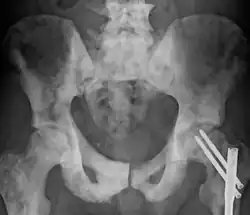

| Sclerosis of the bones of the pelvis due to prostate cancer metastases | |

Osteosclerosis is a disorder characterized by abnormal hardening of bone and an elevation in bone density. It may predominantly affect the medullary portion and/or cortex of bone. Plain radiographs are a valuable tool for detecting and classifying osteosclerotic disorders.[1][2] It can manifest in localized or generalized osteosclerosis. Localized osteosclerosis can be caused by Legg–Calvé–Perthes disease, sickle-cell disease and osteoarthritis among others. Osteosclerosis can be classified in accordance with the causative factor into acquired and hereditary.[2][1]

- Osteogenic bone metastasis caused by carcinoma of prostate and breast

Osteosclerosis can be detected with a simple radiography. There are white portions of the bone which appear due to the increased number of bone trabeculae.